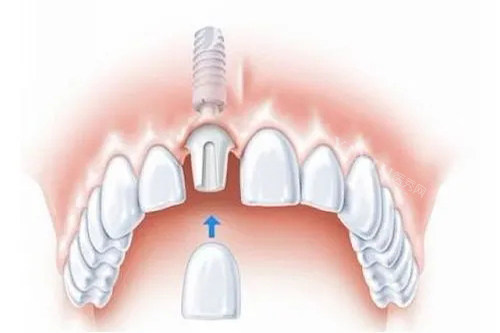

种植牙手术是通过外科手术的方式将人工牙根(种植体)植入缺牙部位的牙槽骨内,经过一段时间(通常为 3 - 6 个月),使种植体与牙槽骨形成牢固的骨结合,然后安装基台、牙冠,从而改善牙齿的形态和功能。在开封河川口腔,经验充足的医生会在术前通过口腔 CT 等新型设备,对患者的口腔状况进行齐全评估,制定个性化的种植方案。

手术时,医生会先对患者进行局部麻醉,以确保在手术过程中患者不会感到明显疼痛。在麻醉起效后,医生切开牙龈,暴露牙槽骨,使用正规工具在牙槽骨上制备种植窝,将种植体植入其中,缝合创口。整个过程中,新型的医疗设备和精细的操作技术,能大程度减少对周围组织的损伤,降低患者的不适。